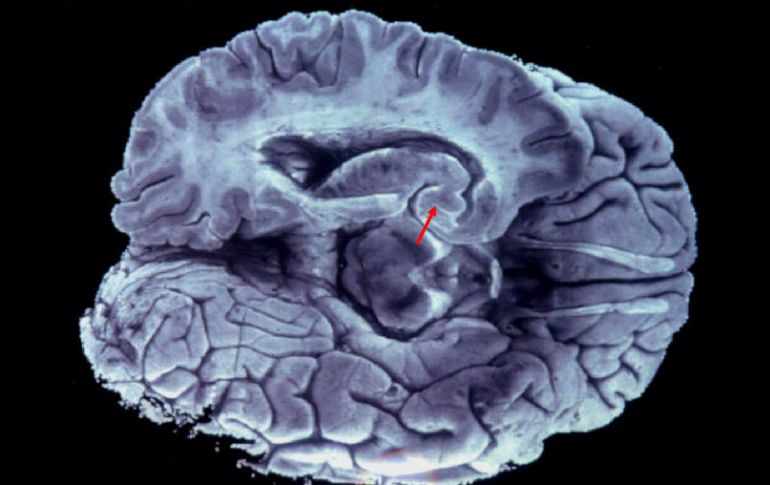

Se trata de una enfermedad crónica y desmielinizante que perjudica al sistema nervioso centra. EFE / ARCHIVO

Se trata de una enfermedad crónica y desmielinizante que perjudica al sistema nervioso central y, por consiguiente, provoca discapacidad debido al daño ocasionado en la mielina que recubre las fibras nerviosas.